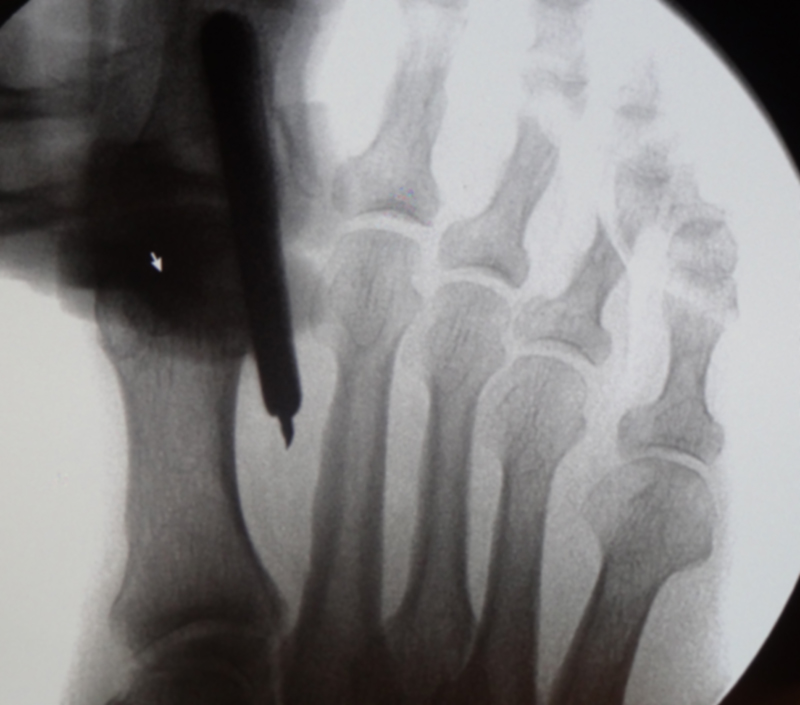

• Bildverstärker für intraoperative Kontrollaufnahmen 3.

• Bildverstärker.

• Positionierung des Bildverstärkers im 90° Winkel zur Fußlängsachse (Abbildung 4).